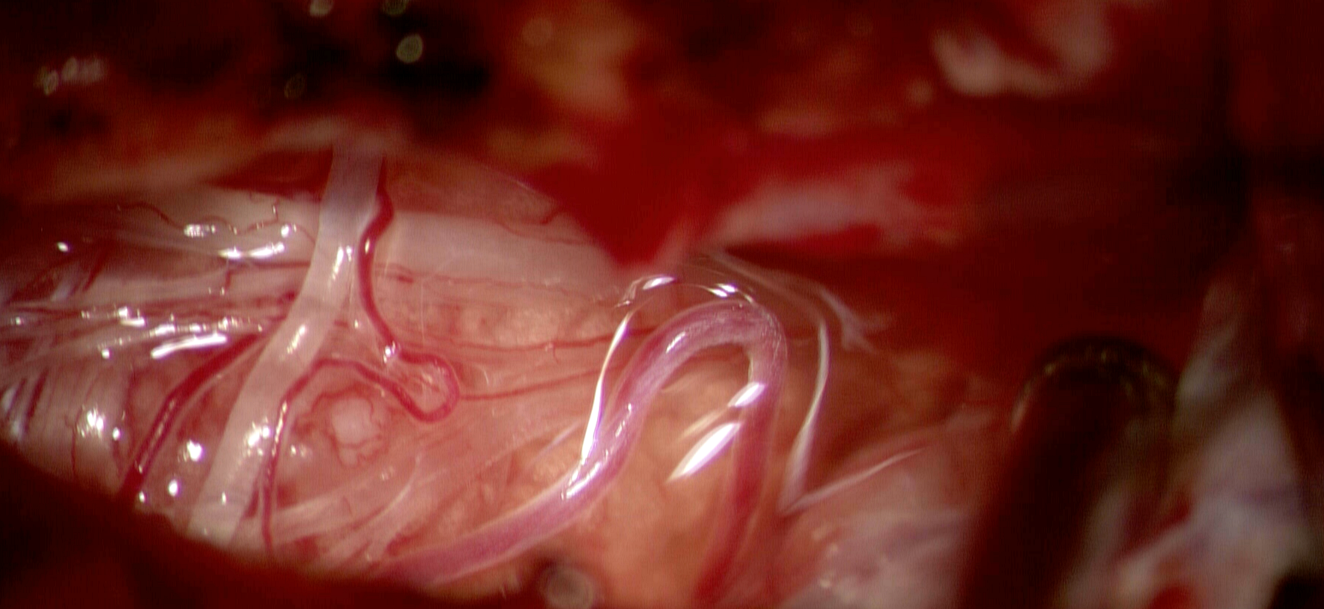

Abordul uzual este cel endoscopic transsfenoidal (prin nas și sinusul sfenoidal) – minim invaziv, eficient și cu risc redus, prin acre se pot aborda cu succes peste 95% din cazuri. Este util mai ales pentru tumorile mici, strict intraselare (microadenoame sau macroadenoame) și are limite în cazul tumorilor mari, extinse supraselar anterior sau lateral, dincolo de planul aretrelor carotide.